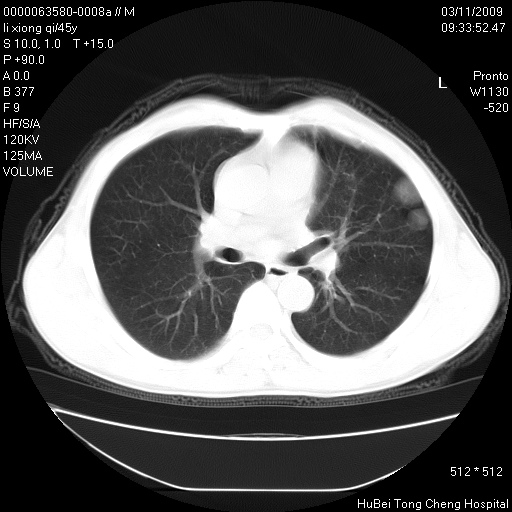

患者 男,45岁。胸痛,咳嗽伴痰中带血1月余。

临床诊断:肺结核?

胸部ct轴位平扫(层厚10mm,螺距1.5,重建间隔10mm),图像如下: